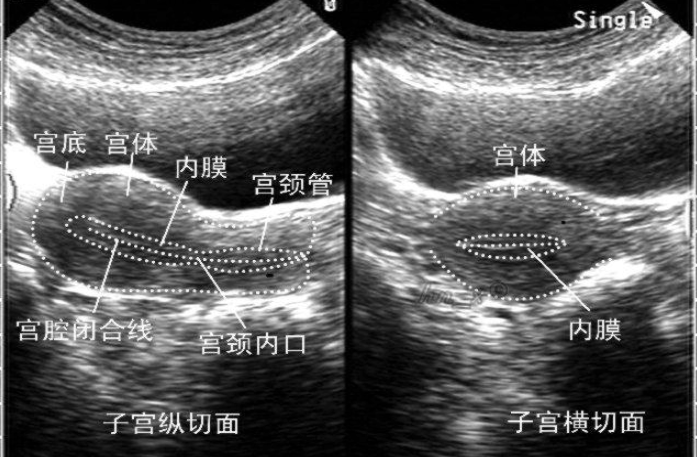

在未怀孕和孕早期(11周以前),此时的子宫位于膀胱的后方,膀胱空虚时,子宫的前方会有肠道,而肠道内的气体会把超声大量的反射回去(简单说就是类似把眼睛蒙上了),从而影响子宫及其内孕囊的呈现,容易误诊、漏诊,此时就需要憋尿(当然此时做阴道彩超是更优于经腹彩超的);适当充盈的膀胱能将子宫前方的肠道推挤开,而尿液作为一种较好的声波传导介质,能使位于后方子宫及其内的孕囊清晰的显示。

膀胱未充盈时(子宫无法清楚显示)

适当充盈膀胱以后,子宫各切面均能清楚显示

首先,做阴道彩超的所有物品都是一人一换(包括臀垫、硅胶套等等),手法也很轻柔;其次,也是很重要的一点,就是阴道彩超不是将探头放进了宫颈甚至宫腔内,而将探头放置于阴道内,不会受到肠道气体的影响,因此阴道彩超也较经腹彩超更能清晰的显示子宫、附件、孕囊的情况,更优于经腹彩超。